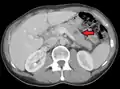

| Illustration showing hematogenous metastasis | |